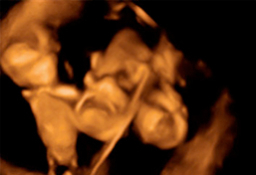

Ecografía de la semana 12

Confirma la edad gestacional y el número de bebés

Los motivos por los que los ginecólogos recomiendan realizar una ecografía en la semana 12 de embarazo tienen que ver con el desarrollo anatómico y el tamaño del feto: ahora es lo bastante grande para comprobar si presenta anomalías. Además, ya se puede ver con claridad si hay uno o dos (o tres) bebés, calcular  la fecha probable de parto teniendo en cuenta la edad gestacional, y confirmar que esta coincide con el desarrollo del bebé. Se puede medir el llamado pliegue nucal (si sobrepasa unos parámetros a veces es indicio de problemas cromosómicos) y, si el bebé se deja, conocer su sexo.